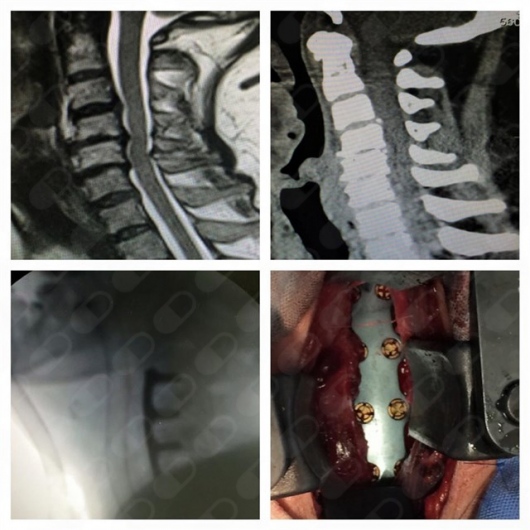

- Cirugía de columna

Fusiones vertebrales por vía posterior

El mejor muy amable te explica cada detalle a detalle el me operó mis cervicales